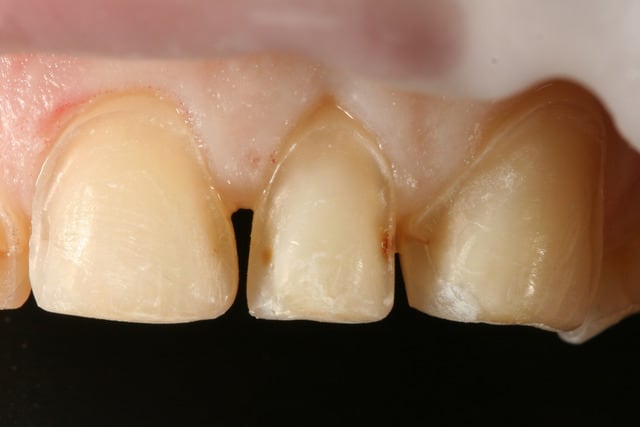

pour les points de caries que j'ai découverts entre 22 et 23, j'ai essayé d'en enlever un maximum en préparant, mais c'est vrai qu'en regardant les photos ça semble un peu limite sur la 22, peut être que j'y repasserait un coup de fraise avant de coller les facettes.

je pense pas que ça puisse ce voir, c'est quand même assez loin en interdentaire.

par contre j'ai plus peur du risque de carie derrière la facette effectivement, j'aurais du creuser un peu plus et mettre un peu de compo

juste une petite remarque , au niveau du toboggan mesial sur 23, j'ai l'impression que l'angle est trés marqué. n'y a t il pas un risque de fracture de la céramique à ce niveau ?

oui, je me suis fait la même remarque en voyant les photos, j'ai fait ça en allant chercher la zone cariée et j'espère que le fait que ce soit de l'emax et pas de la feldspathique pure compensera mon erreur

par contre, je me dis que je suis resté trop supra-gingival sur mes préparations, ça se voit trop, même si la patiente découvre peu, elle découvre un peu et j'aurais du aller plus juxta.

Le problème, ce n'est pas tes prep, c'est le choix du matériau avec lequel ont été faites les facettes : trop opaque. Le contraste entre facette et dent naturelle est trop important. Il aurait fallu un matériau plus translucide et mimetique. Un beau collage fait le reste...

c'est de l'emax ... à moins de faire du feldspathique, je pense pas qu'on puisse faire plus translucide

mais là à l'essayage c'est mis avec un ciment provisoire, donc la lumière passe pas, ça va mieux une fois collé

voilà le resultat collé

je suis resté trop supragingival, mais la patiente est très contente (ouf, c'est l'essentiel !)